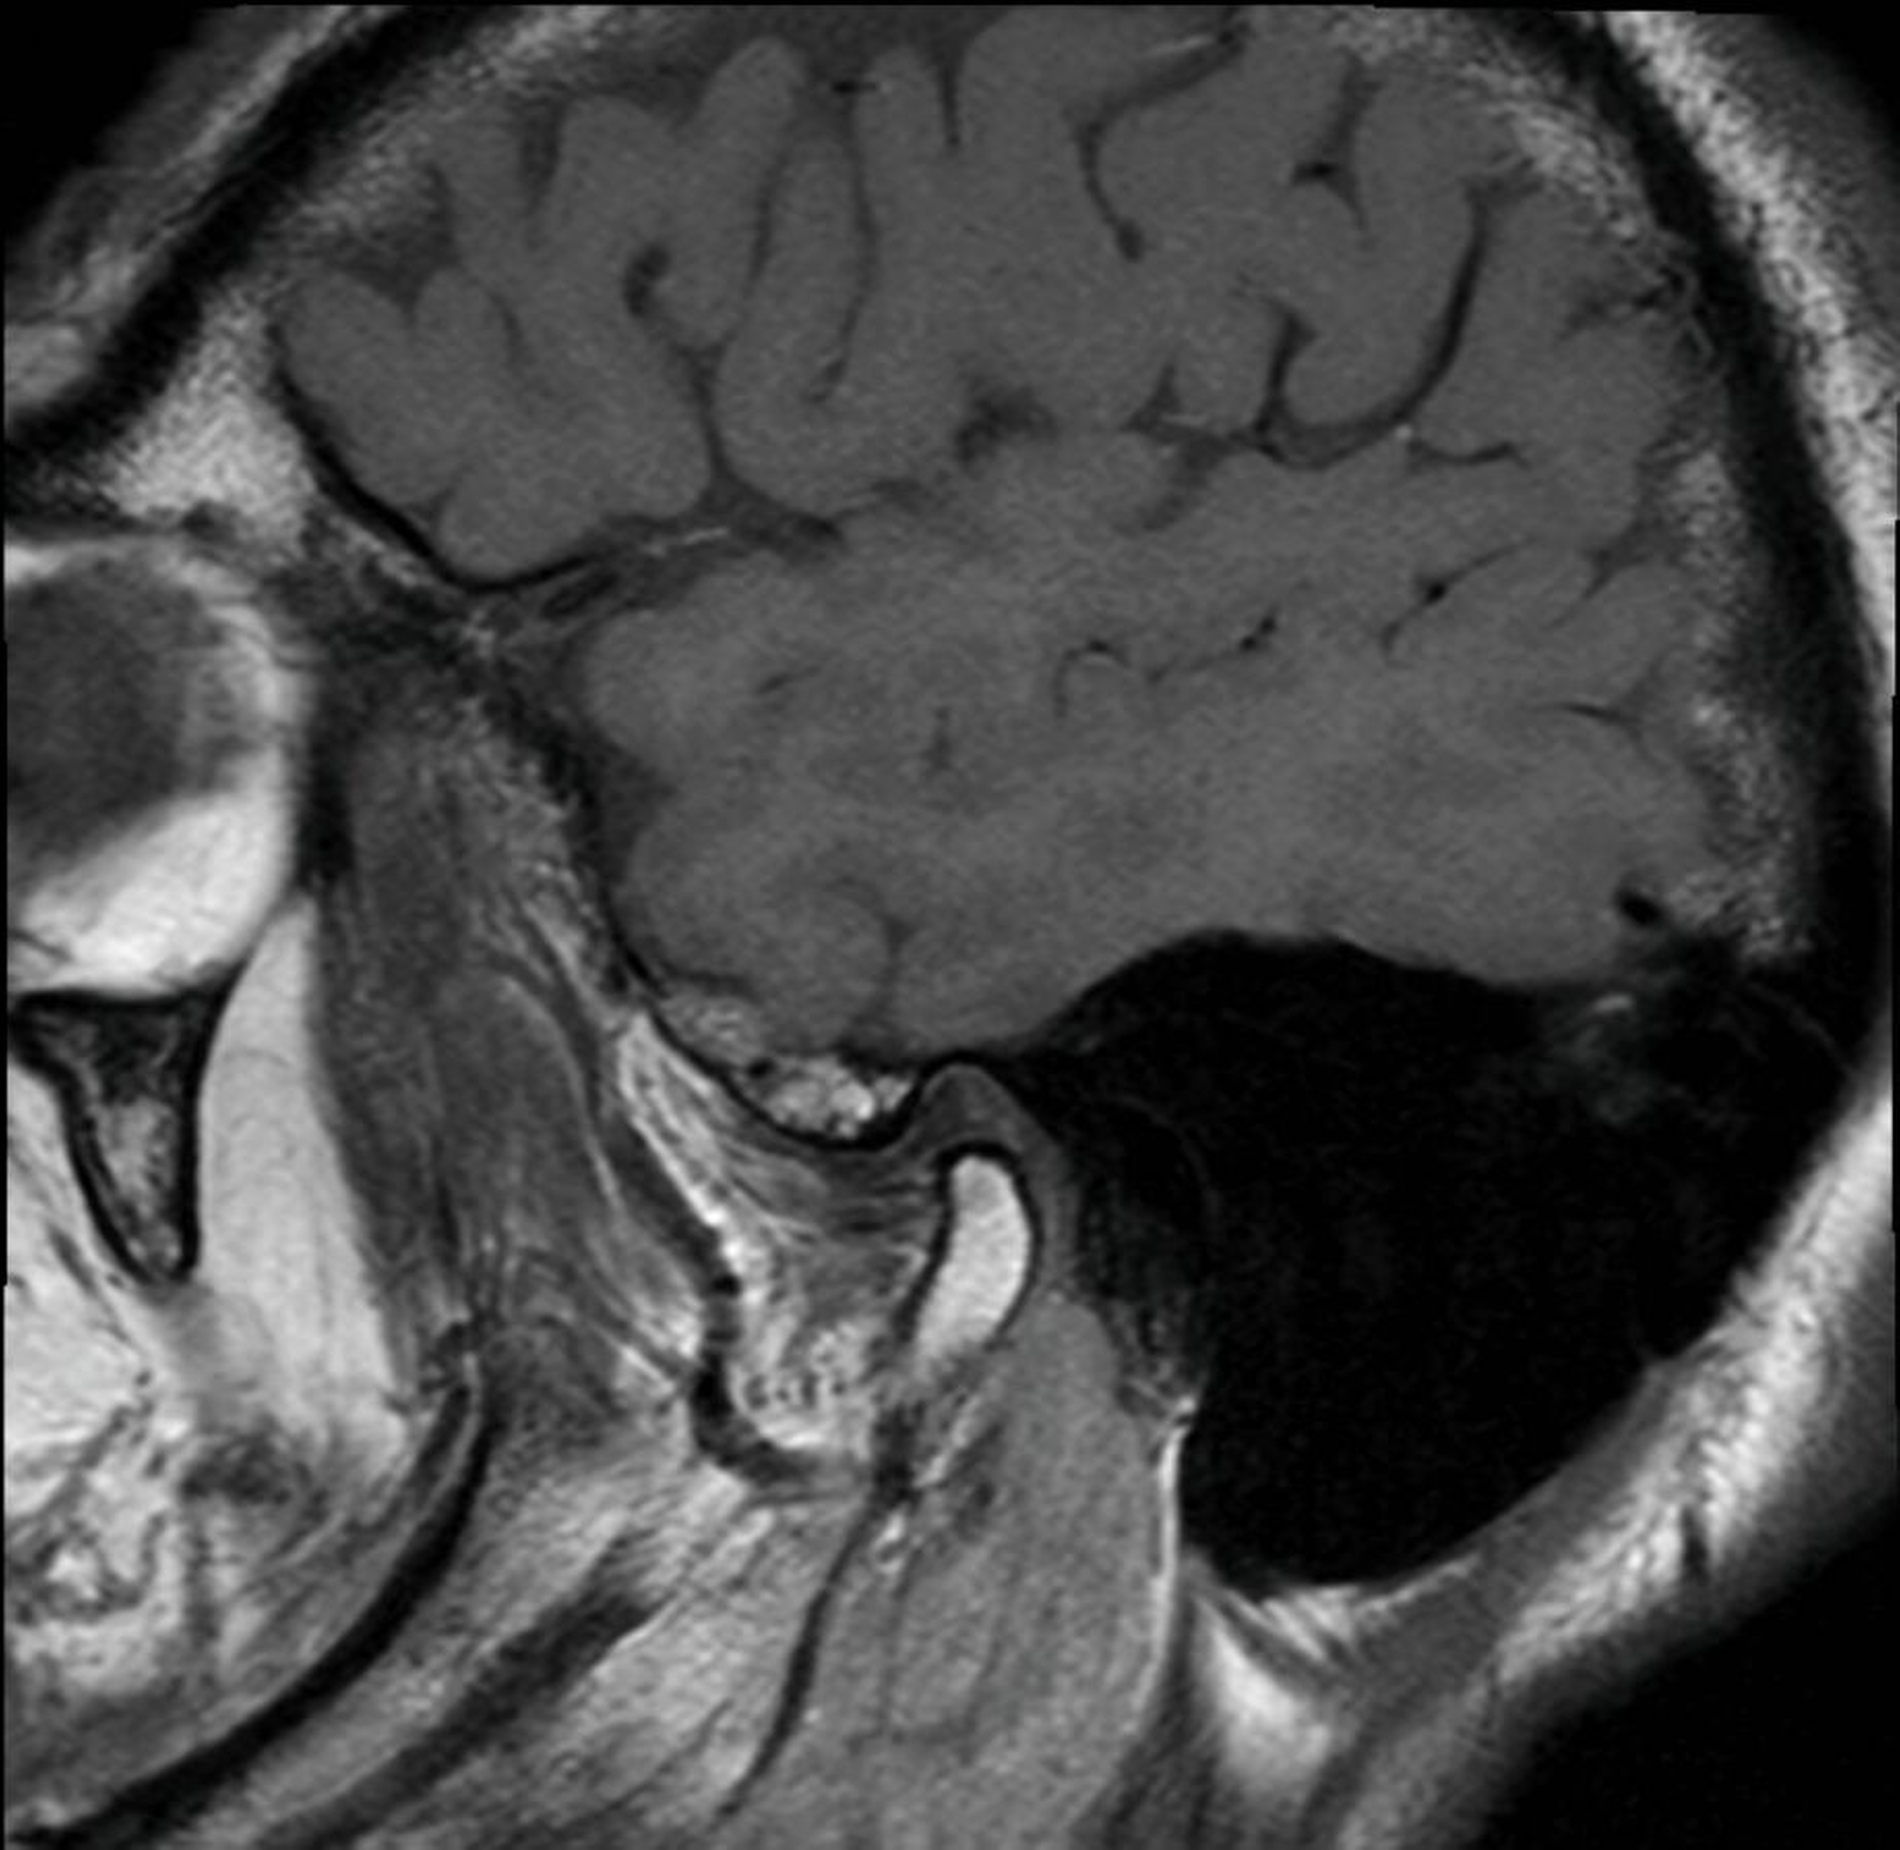

Bei der klinischen Inspektion zeigt sich eine erythematöse, narbig imponierende Hautveränderung präauriculär im Bereich der Kiefergelenke beidseits. Zusätzlich waren eine Hyperkeratose und eine schuppige Komponente zu erkennen (Abbildungen 1 und 2). Auf Palpation zeigte sich der präauriculäre Bereich auf Höhe der Kiefergelenke druckdolent. Während der Funktionsdiagnostik war der rechte Condylus mandibulae deutlich hypermobil. Knack- oder Reibegeräusche waren nicht zu hören. Gleichzeitig war eine Deviation zur linken Seite bei der Mundöffnung zu beobachten. Die orale Mundschleimhaut erschien unauffällig bei Abwesenheit von Blasen oder Erosionen. In der alio loco angefertigten MRT-Aufnahme, die durch den Hauszahnarzt entsprechend der aktuellen Literatur [Schmidt et al., 2022; Neff, 2021] angefordert und vom Patienten mitgebracht wurde, zeigte sich die Struktur des Gelenks und des Diskus regelrecht (Abbildungen 3 und 4). In den Aufnahmen während der Kieferöffnung war lediglich eine Hypermobilität des rechten Condylus mandibulae zu erkennen (Abbildung 5). In der T1-Wichtung waren keine Infiltrationen oder entzündliche Veränderungen des präauriculären Weichgewebes zu sehen.